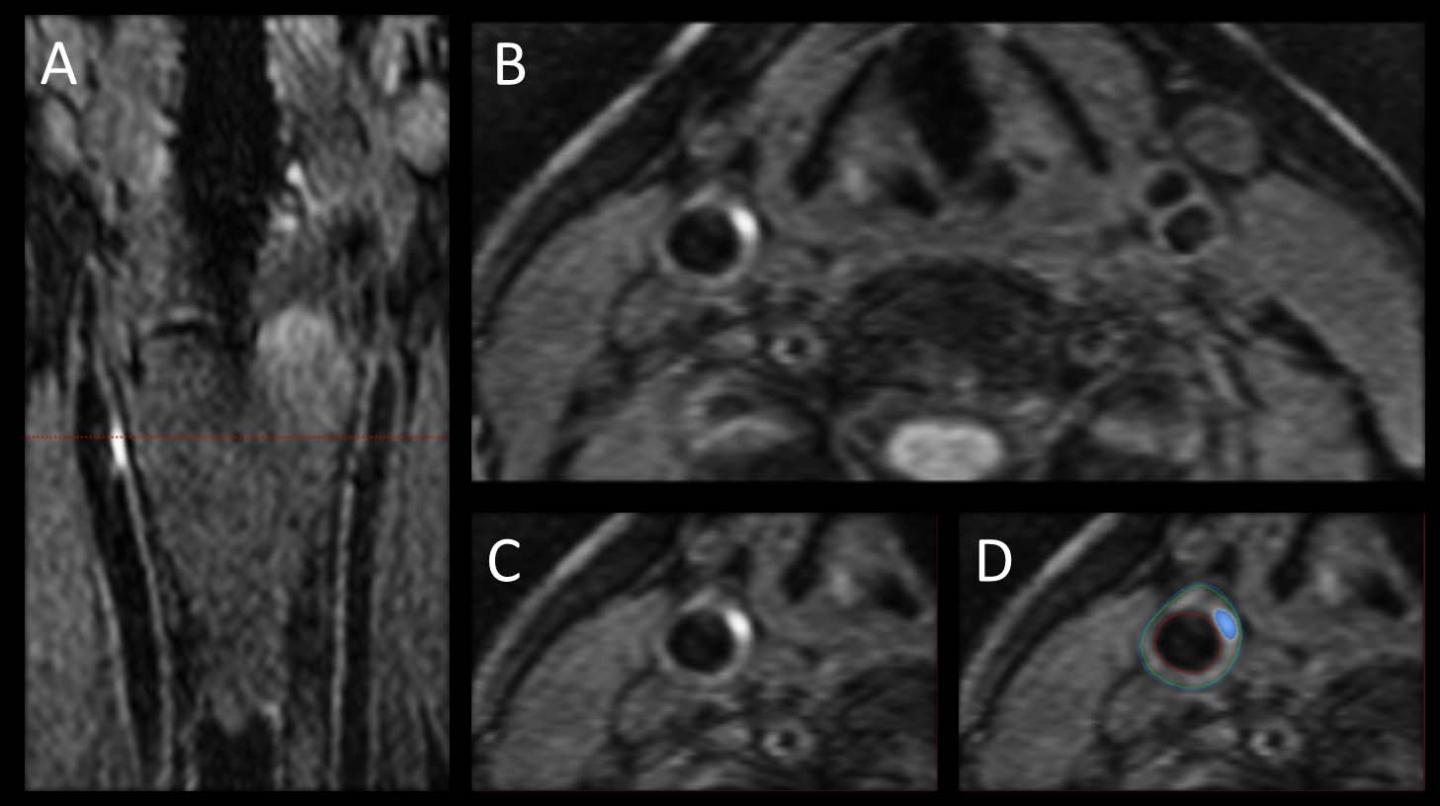

For the new study, researchers used 3-D MRI to study the carotid arteries for evidence of intraplaque hemorrhage (IPH), an indicator of advanced atherosclerotic disease.

Dr. Maraj and colleagues focused their study on people with diabetes, a group already facing a significantly increased risk of strokes with worse outcomes than the non-diabetic population. They used 3-D MRI to investigate the prevalence of carotid IPH in 159 asymptomatic type 2 diabetic patients, average age 63, recruited from a dietary trial between 2010 and 2013.

Of the 159 patients imaged, 37, or 23.3 percent, had IPH in at least one carotid artery. Five of the 37 patients had IPH in both carotid arteries. IPH was found in the absence of carotid artery stenosis, or narrowing, and was associated with an increased carotid artery wall volume as measured by 3-D MRI.

While 2-D MRI has been used for more than a decade to identify and characterize carotid artery plaques, the 3-D method brings an extra level of imaging power, Dr. Maraj noted.

"The advantage of 3-D MRI is you can image the entire carotid artery and pinpoint the area of interest over a shorter period of time compared with multiple 2-D sequences," he said.